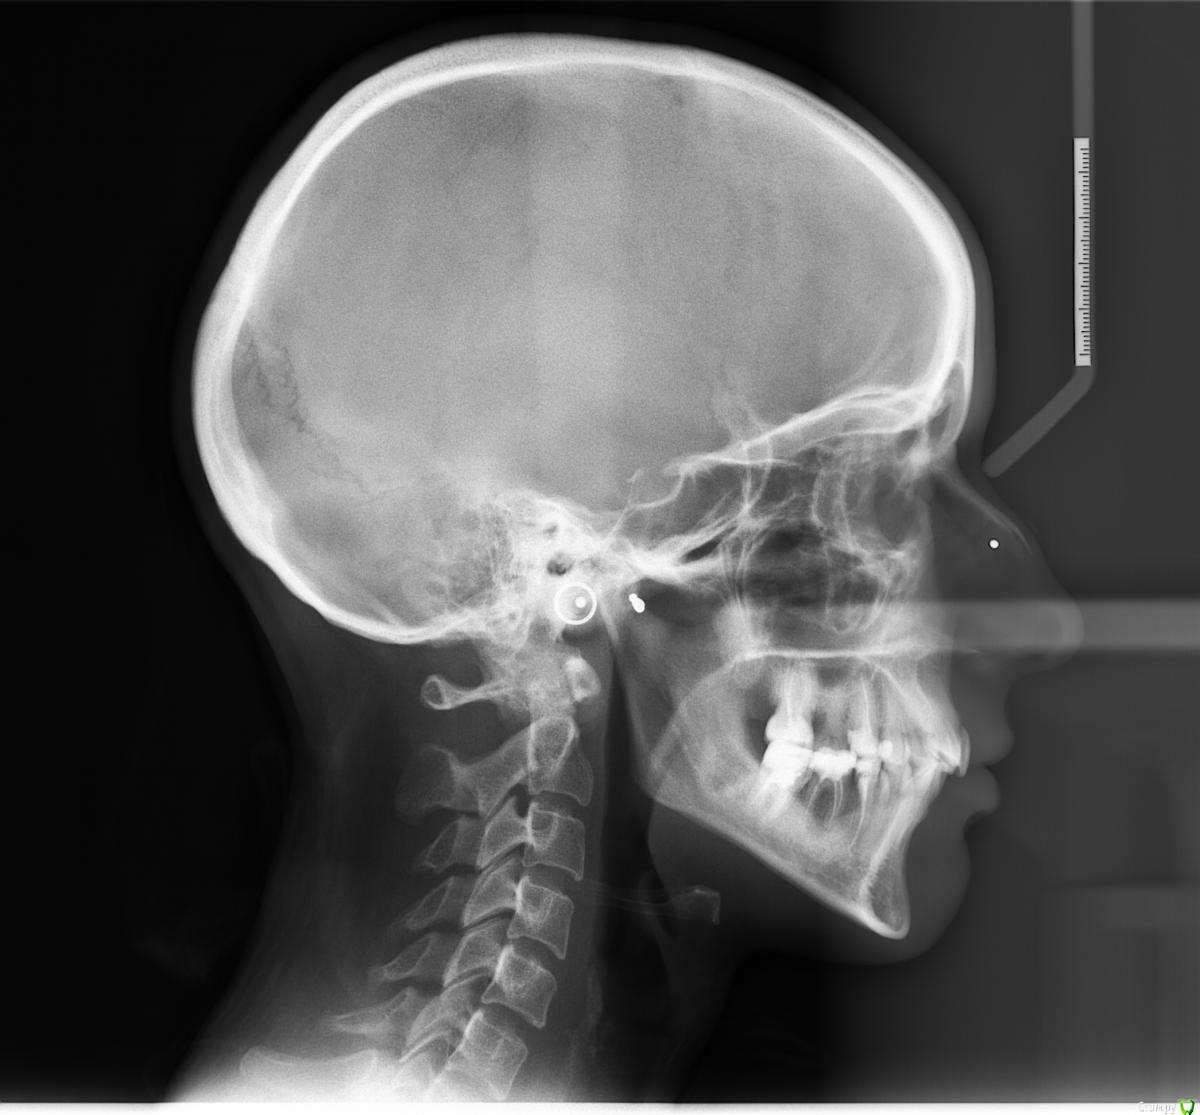

Afffinity Опубликовано 13 декабря, 2016 Автор Поделиться Опубликовано 13 декабря, 2016 Вот именно в чем в принципе сомневаетесь? и на моделях надо указывать анатомический центр, тогда сразу понятнее станет чего и куда и на сколько. ну Вы хотя бы свои мысли озвучили бы, расчет трг, характер асимметрии (в каком положении головки, что на КТ?) ... полностью Вам не распишут план, вопросы более конкретные попробуйте задать для коллегЕсли кратко то по расчетам ТРГ 2й скелетный класс, в цифрах завтра распишу. Прошу прощения что сразу не выложил. 2е, смущает смещение центральной линииПланируем установить систему Damon Q. Самый главный вопрос, возмножо ли в данном случае обойтись без удаления премоляров? Ссылка на комментарий